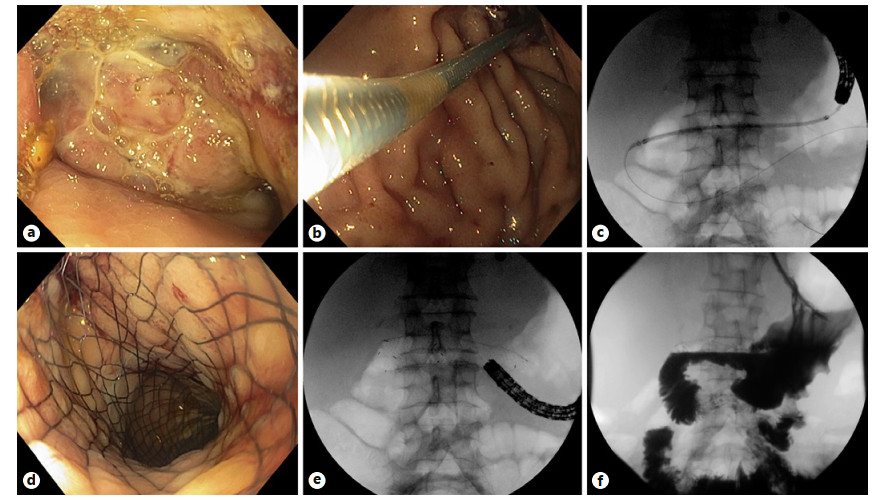

Abstract: Self-expandable metal stents (SEMSs) are frequently utilized for palliation of malignant gastric and/or duodenal outlet obstruction (GDOO). Re-establishing luminal patency with accurate SEMS positioning while limiting migration and adjacent tissue injury is an important technical consideration and aim. The duodenal HANAROSTENT® was introduced in the USA in 2019 and developed with these challenges in mind. As the first center in the USA to deploy the duodenal HANAROSTENT® in clinical practice, we herein examine our early experience with its use. Specifically, we describe 7 consecutive cases of malignant GDOO in which a duodenal HANAROSTENT® was placed for on-label use, defined as palliative treatment of malignant gastric and/or duodenal obstruction. All stents were 22 mm in diameter, with 5 being 90 mm and 2 being 120 mm in length. Technical and clinical success with duodenal HANAROSTENT® placement were achieved in all 7 cases (100%). In no case was stent adjustment required post-deployment. There were no stent-related adverse events, and no subsequent endoscopic procedures were necessary in any of the patients during a mean follow-up of 5 months (range 1–12 months). In summary, the duodenal HANAROSTENT® appears to perform well and be a promising alternative to other available duodenal SEMSs. As experience in the USA with this newly introduced duodenal SEMS grows, multicenter prospective data should be collected to better establish its relative safety and efficacy.